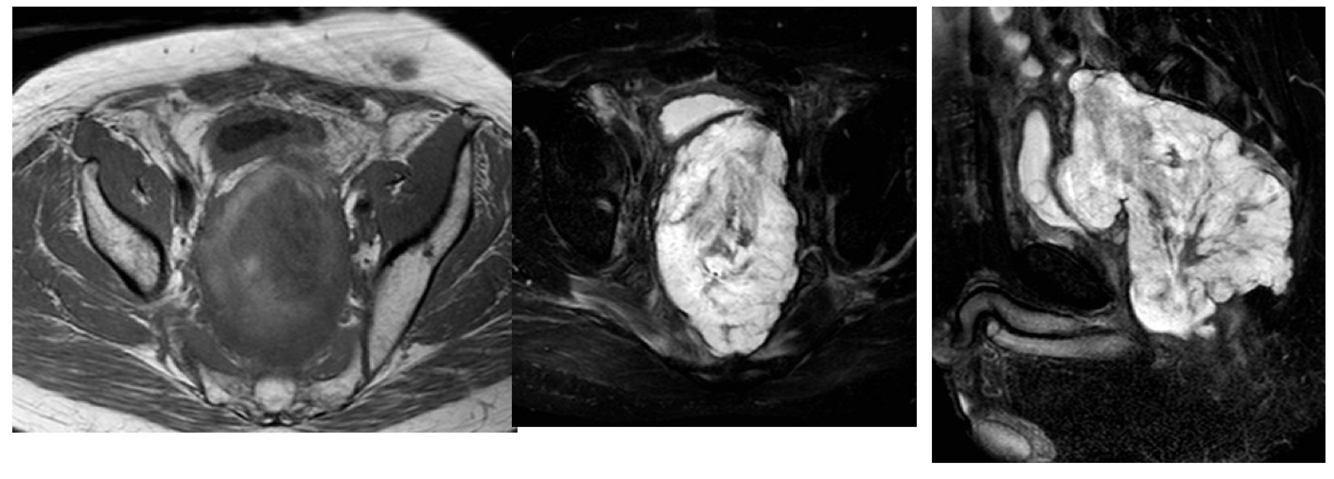

What this be?

Endometrial carcinoma